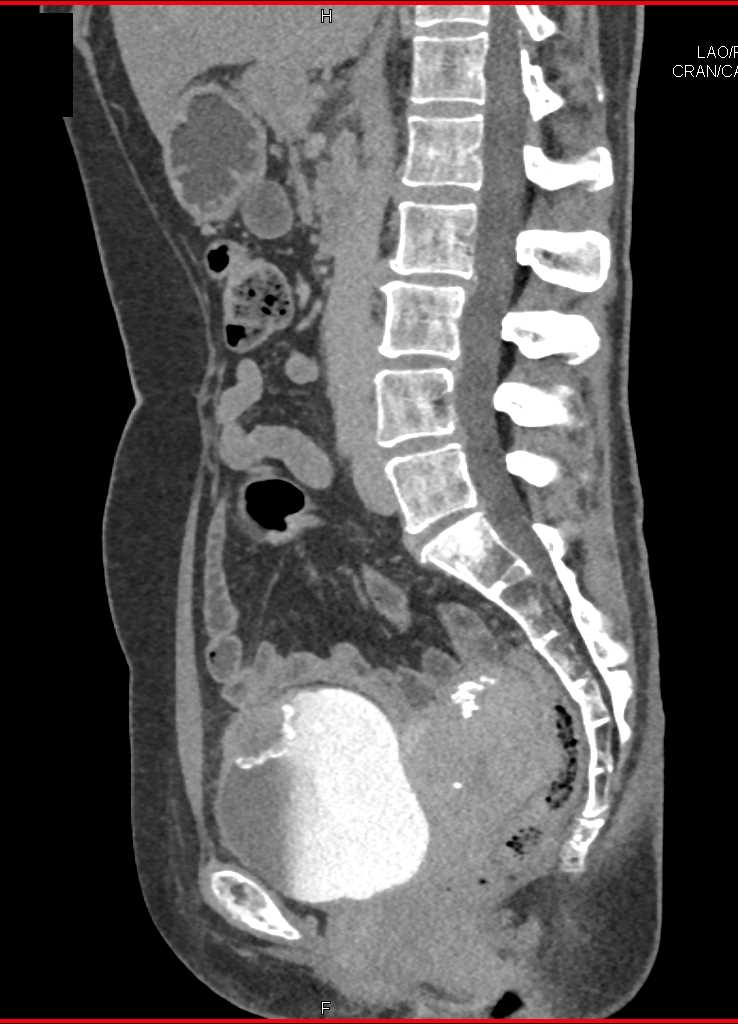

Urachal Carcinoma of the Bladder